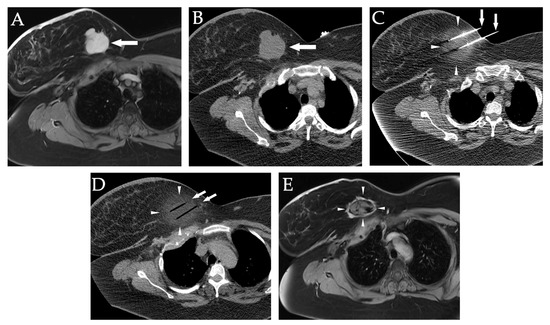

10. Primary and Metastatic Lung Tumors

12. Primary and Metastatic Soft Tissue Tumors